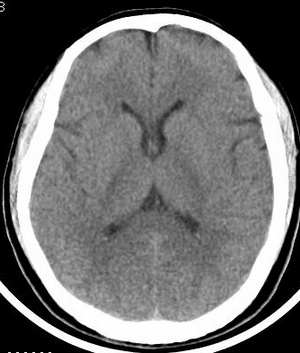

患者 男 45岁,头晕月余,无其它不适。

请大家看看大脑大静脉池里的条状影是什么?脑内静脉?

我觉得是生理改变。 应该是血管影 建议做cta检查!

未见明显异常。